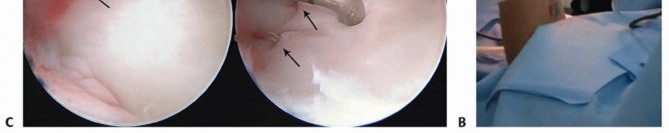

TECH FIG 3 • Wrist arthroscopy to address TFCC injury. A. The patient is placed supine with an arm board; a strap is used to securely fashion the arm to the table. A boom is placed on the contralateral side. B. Finger traps are positioned, the weight is attached. Fluoroscopy is used to access DRUJ reduction. C.

TECH FIG 4 • Ulnar styloid fracture fixation. A. The distal ulna is exposed at the ulnar styloid and a 3.5-mm drill guide is used to reduce the fracture and to pass K-wires. B. Anteroposterior (AP) radiograph of a tension band open reduction internal fixation (ORIF). C. Tension band construct with a suture anchor. D. ORIF with plate and screw construct. E. Loss of fixation using headless compression screw. A transverse (dorsal to volar) 2-mm drill hold is made proximally through the ulnar neck, and a 27-gauge wire is placed through the TFCC at its insertion on the ulnar styloid.A figure-of-eight bend is made, and one limb is passed volar to dorsal through the transverse bone hole, whereas the other is passed dorsal to volar.The wire is then twisted to tension, and the pins are bent and cut. The bent tips are pointed radially and driven into the styloid with a small bone tamp, capturing the wire ( TECH FIG 4B).Alternatively, after placing the pins through the ulnar styloid, a 2-0 suture anchor can be placed in the ulnar neck and the sutures passed in opposite directions around the styloid. The limbs are tied down to the medial ulnar shaft, and the pins are bent and cut as previously discussed ( TECH FIG 4C).Plate and screw construct may also be used for buttress effect, but implant prominence must be considered ( TECH FIG 4D).Headless compression screw fixation is advocated by some. We have noted frequent failure and malreduction with this technique. If screw fixation is used, bicortical fixation is recommended ( TECH FIG 4E).If the DRUJ is still unstable, proceed with radioulnar transfixation pinning. Wound closure, sterile dressings, and long posterior splint are applied.P.250PEARLS AND PITFALLS